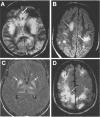

Infections in the central nervous system (CNS) are caused by a wide range of microorganisms resulting in distinct clinical syndromes including meningitis, encephalitis, and pyogenic infections, such as empyema and brain abscess. Bacterial and viral infections in the CNS can be rapidly fatal and can result in severe disability in survivors. Appropriate identification and acute management of these infections often occurs in a critical care setting and is vital to improving outcomes in this group of patients. This review of diagnosis and management of acute bacterial and viral infections in the CNS provides a general approach to patients with a suspected CNS infection and also provides a more detailed review of the diagnosis and management of patients with suspected bacterial meningitis, viral encephalitis, brain abscess, and subdural empyema.